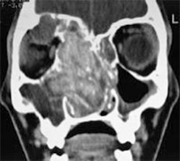

All’esame endoscopico si evidenziano secrezioni naso-sinusali dense e viscose di colorito bruno-giallastre, con tappeto di eosinofili e scarse ife fungine all’esame microscopico spesso associate a poliposi nasale massiva mono o bilaterale altamente recidivante. La TC documenta la presenza di poliposi e di secrezioni patologiche associate ad aree focali di elevata densità. In questo caso il trattamento è sia medico, con somministrazione topica di farmaci corticosteroidei e antimicotici, che chirurgico, generalmente con tecnica endoscopica.